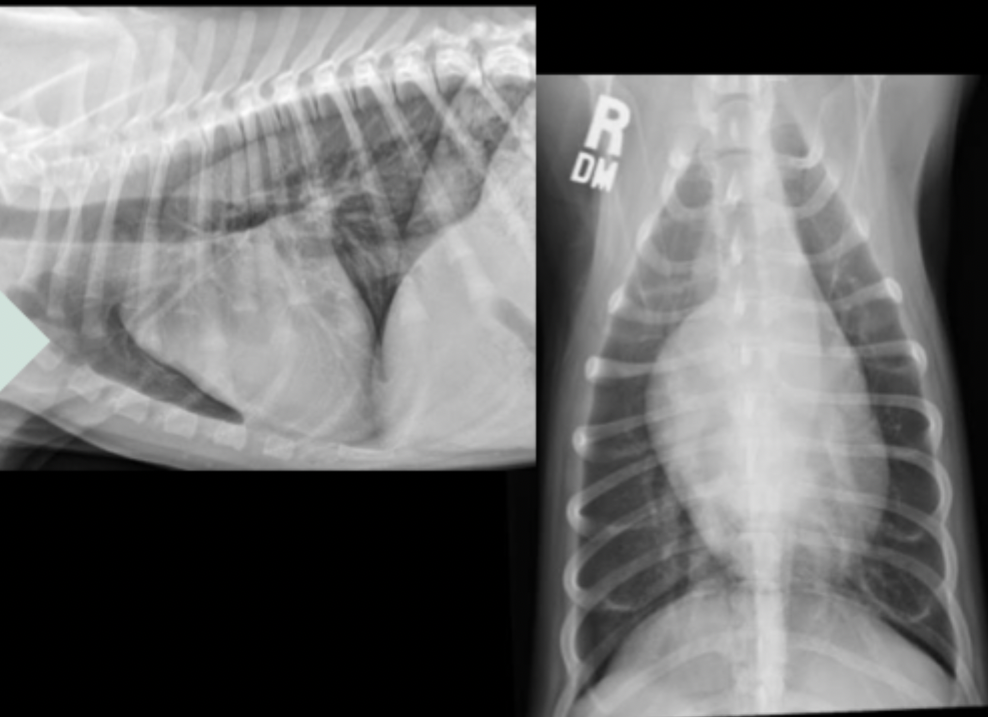

What can be seen in these cat radiographs?

Nothing, these radiographs are normal

What radiographic changes can be seen with feline hypertrophic cardiomyopathy?

heart may be normal

mild to severe left atrial enlargement

apex often displaced rightward

classic “valentine shaped” heart

What can be seen on these feline radiographs?

left atrial enlargement